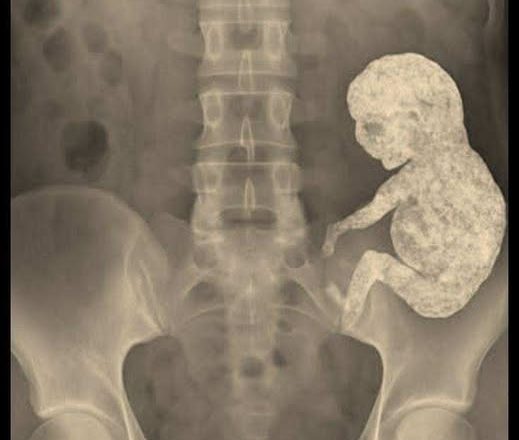

Une forme apparut sur l’écran. Recroquevillée comme un bébé dans le ventre de sa mère. Une masse dense et minéralisée. Un lithopédion. « Un enfant de pierre », dit le chirurgien. Et il se tut, comme si les mots avaient perdu leur sens.

Quand, des années plus tard, elle accepta enfin l’opération, les chirurgiens se préparèrent à l’extraction, comme pour lui dire adieu. Un silence de mort régnait dans la salle d’opération. Après l’opération, l’un des médecins admit que, pour la première fois de sa vie, il éprouvait de la compassion pour « l’objet extrait ». Il avait quelque chose d’humain en lui : une forme, un symbole, une signification.

Rosa se réveilla dans une chambre d’hôpital et demanda à voir ce qu’elle avait porté en elle pendant trente ans. Une petite masse grisâtre et irrégulière, comme une figurine de marbre. Elle la caressa du bout des doigts et dit : « C’est encore chaud. »